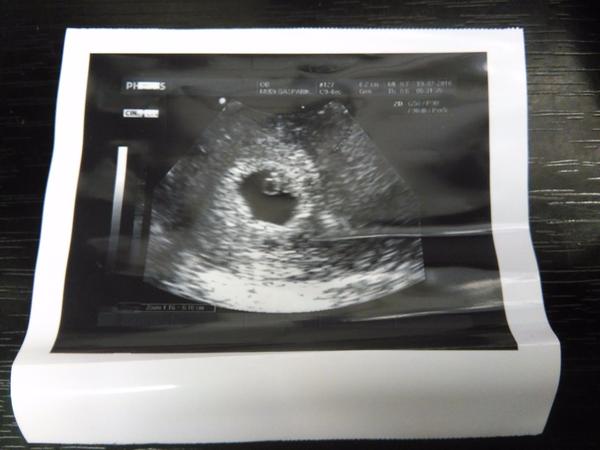

@liwinqua to je super, ze uz bolo aj srdieckoa celkom skoro. 🙂 pekna fotka.

@14nunu10 ano, aj mi napadlo, ze to tak nejak bude. no je fajn, ze to vobec vidno., asi kazdy dr. nema take sono, aby to takto dokladne zobrazil, teda aspon myslim. neviem, lebo z predosleho tehu takuto foto nemam. dr. som vzdy musela ziadat, aby mi urobil snimku. no takze aj ty este na foto cakas. ja mam noveho dr. a vraj je celkom fajn, tak uvidime, ako sa o nas bude starat.